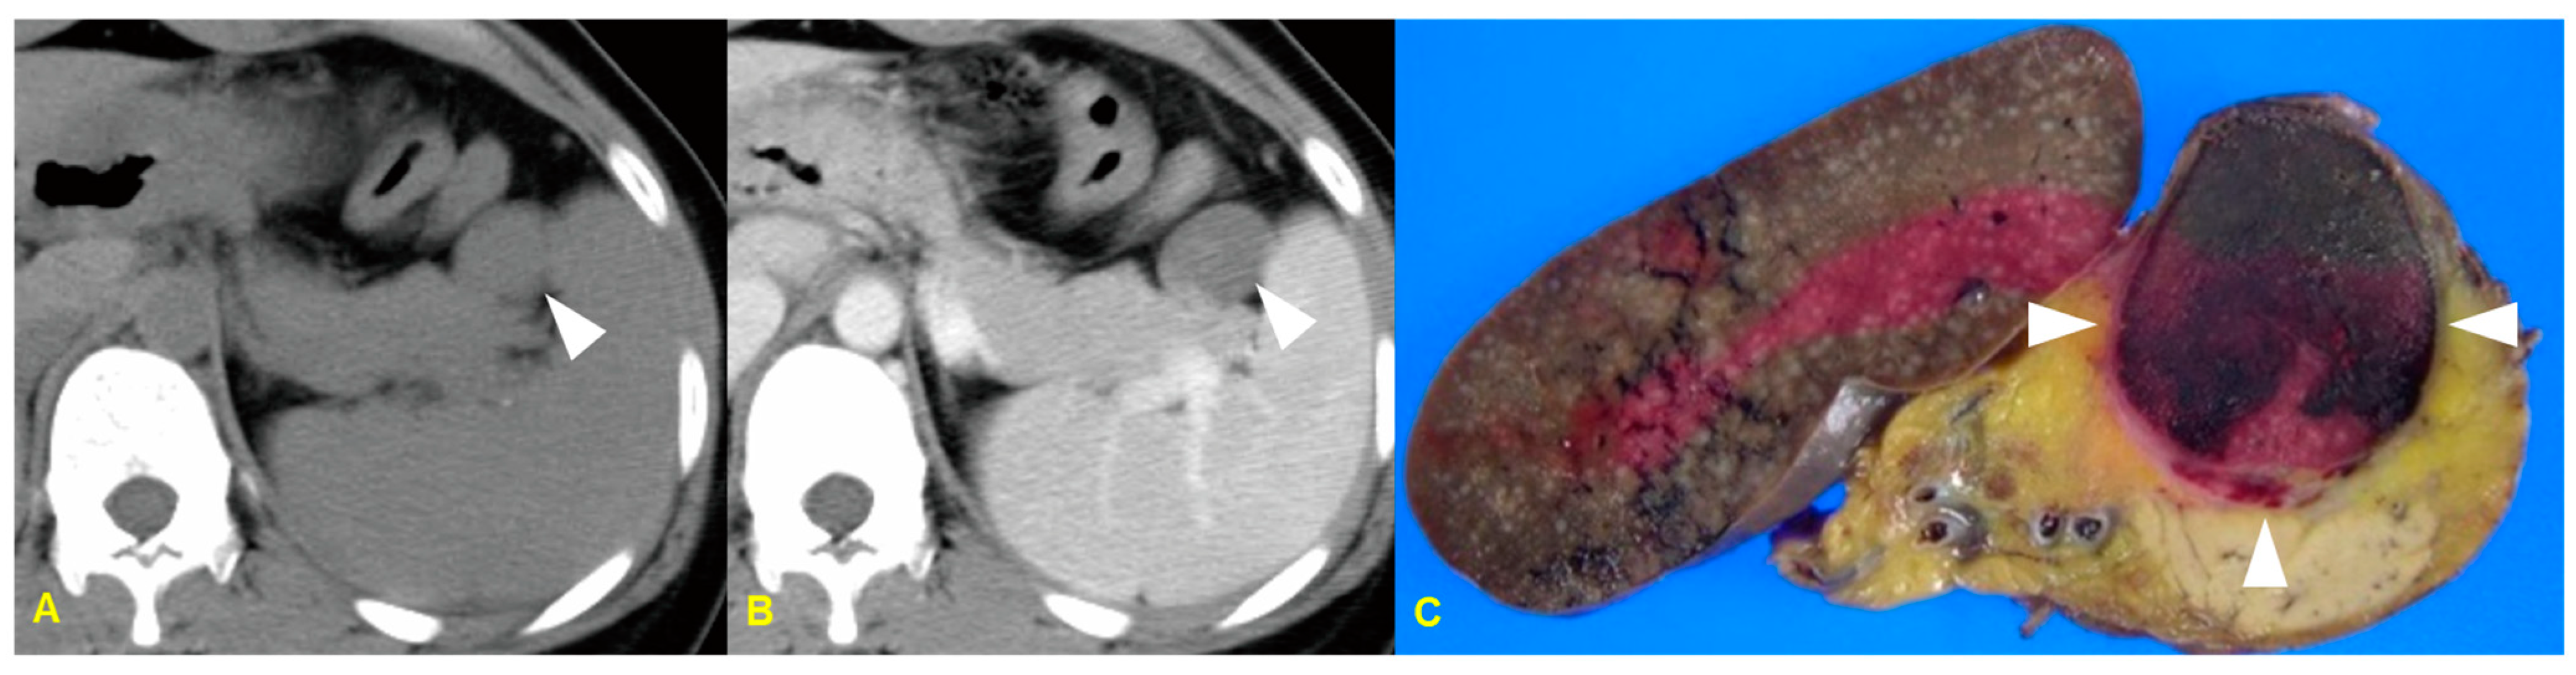

10. Infarcted Intrapancreatic Accessory Spleen

10.1. Imaging Finding

10.2. Differential Diagnosis

| Infarcted intrapancreatic spleen | Enhancement pattern: poor enhancement/ Sometimes, peripheral enhancement by capsular vessels |